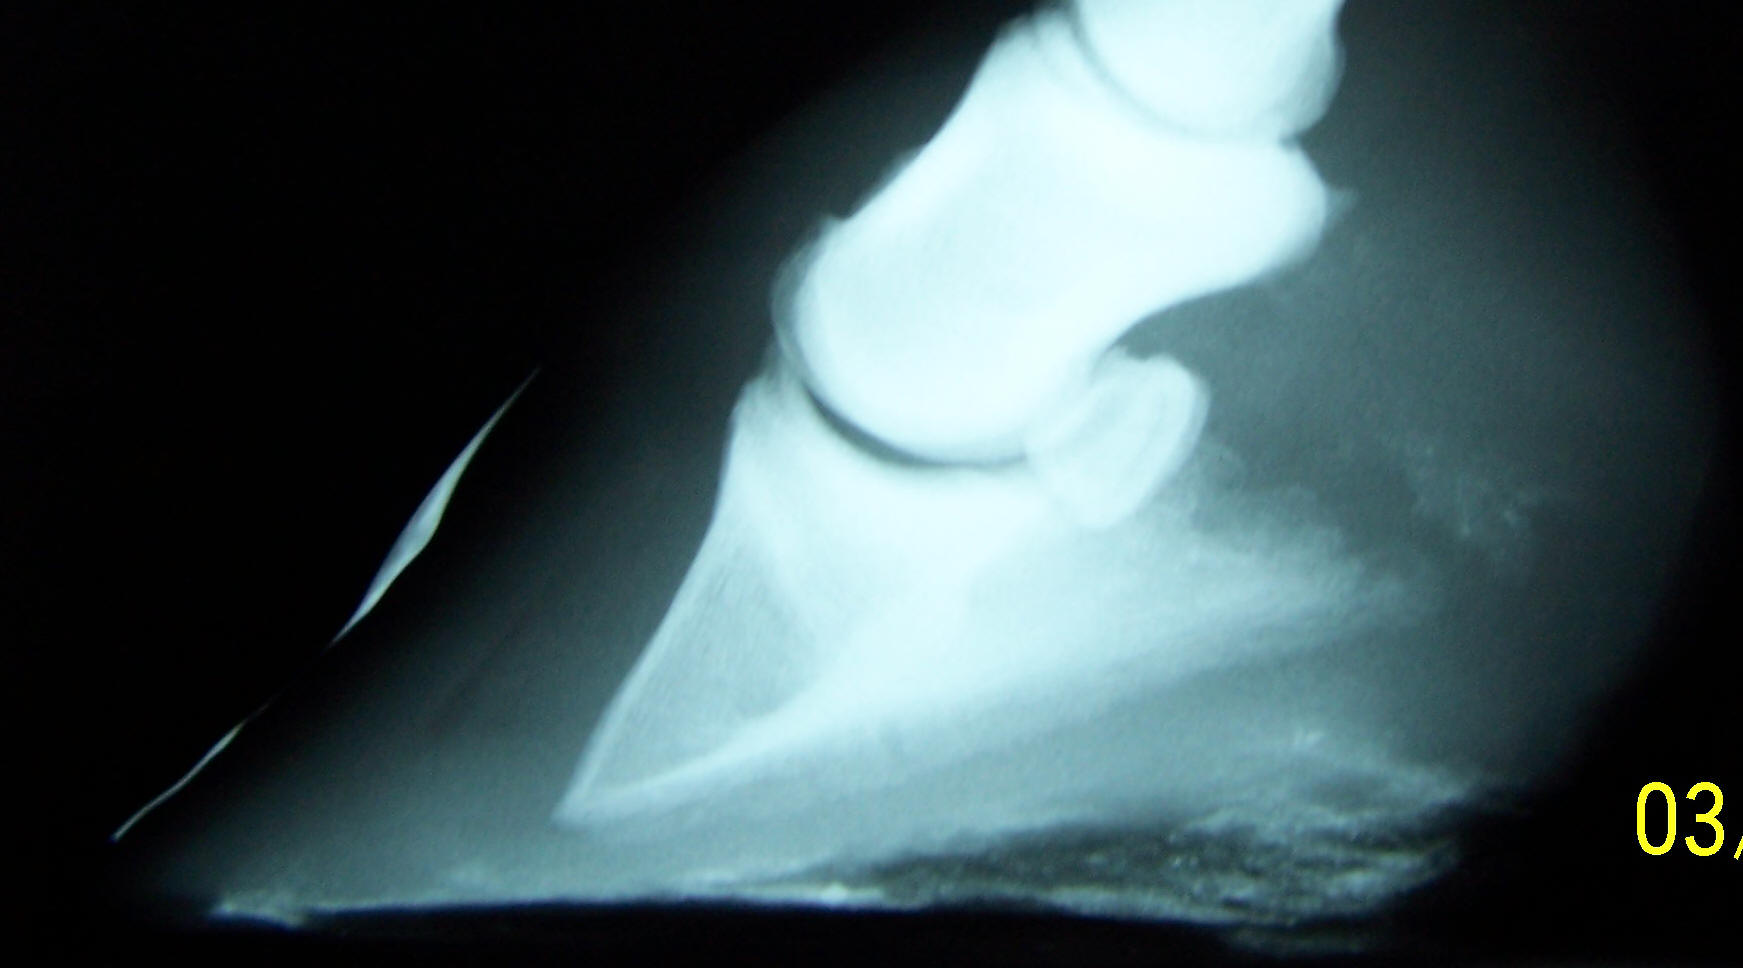

the shape of the soles and particularly, the height of the

collateral grooves from the ground. The wild hoof below has a

wire placed in the bottom of the collateral groove to help you

visualize this on the radiograph.